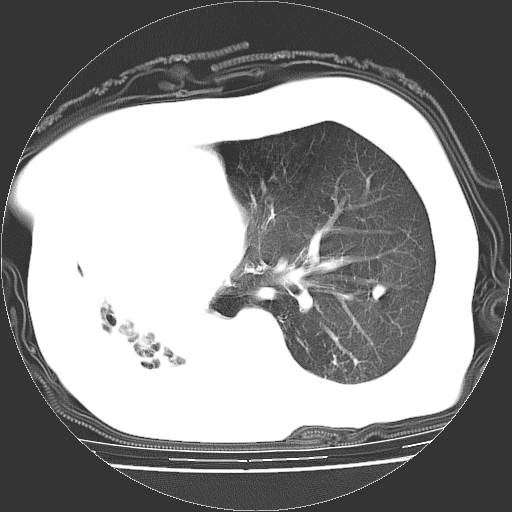

标题: CT23991:女,72岁,咳嗽、憋气一周。 [打印本页]

女,72岁,咳嗽、憋气一周,十年前曾患肺结核及胸膜结核。

右侧毁损肺,右侧纵隔疝

右侧毁损肺,右侧纵隔疝,左肺代偿!

右侧肺硬变,左肺代偿气肿。

1.右侧损毁肺伴胸膜钙化,2.左肺小结节灶,良性可能大,注意复查。3.肝脏左叶囊肿。4.先天性一侧肺不发育待出外(右侧胸廓无明显塌陷)。对比原片应该非常有帮助。

右侧肺毁损,左肺代偿性肺气肿,纵隔疝。